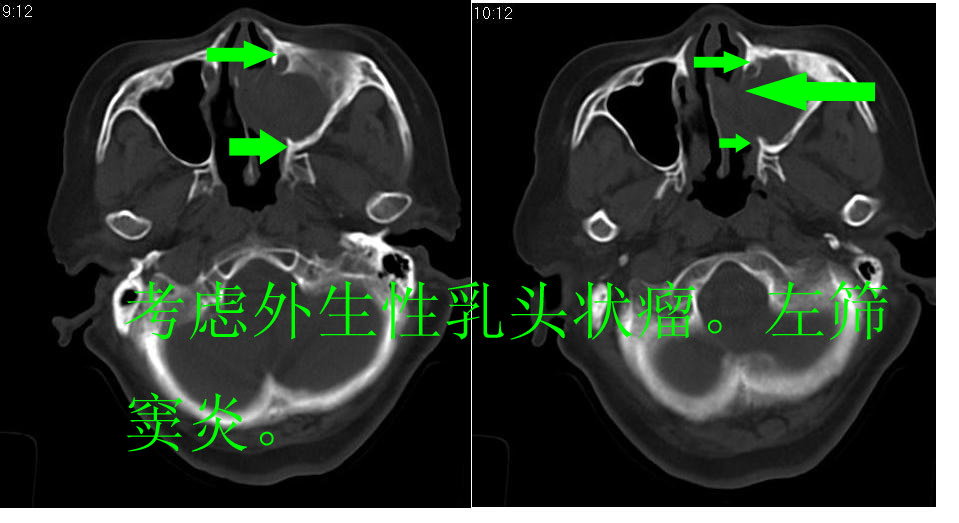

女 70岁,左侧上颌窦腔内肿物。

左侧颌窦内可见高密度影充填,窦壁增厚 考虑 左颌窦囊肿 慢性炎症

左侧上颌窦内软组织影,略呈膨胀性,窦壁骨质增生硬化,考虑为黏膜下囊肿.左侧筛窦炎

从病灶生长方式分析,更支持:上颌窦囊肿。

左侧上颌窦内软组织密度影,窦壁骨质增厚,密度增高,窦口扩大,考虑左侧上颌窦慢性炎症,息肉样变。

左侧上颌窦窦内可见高密度影充填,窦壁增厚,考虑左上颌窦窦囊肿,慢性炎症.